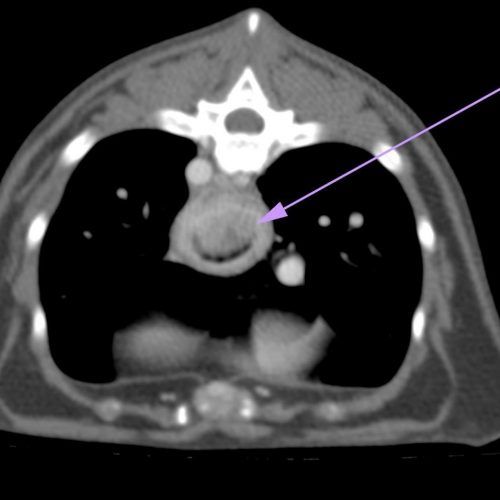

TC MULTISTRATO